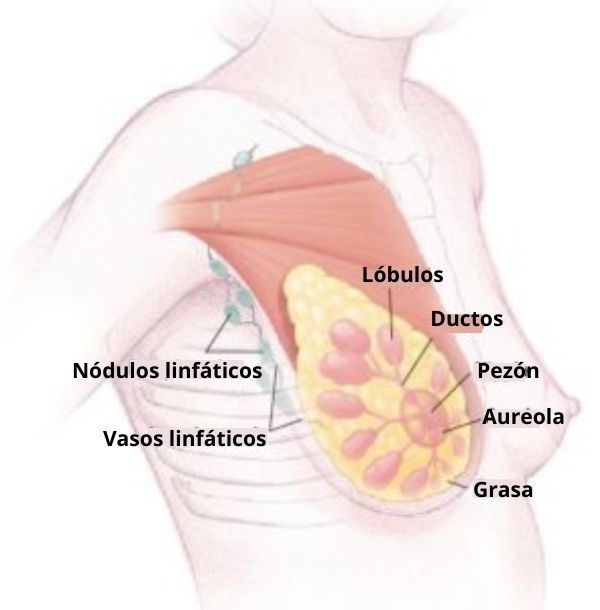

– Glándulas apocrinas: son aquellas glándulas cuyas células liberan parte de su contenido citosólico con cada secreción (ejemplo son las glándulas mamarias).

Estas glándulas se encargan principalmente de la liberación de hormonas, las cuales son distribuidas hacia los distintos órganos “diana”. Las glándulas endocrinas más importantes del cuerpo son las glándulas suprarrenales o adrenales, la hipófisis, la tiroides, la paratiroides y la glándula pineal, los ovarios, la placenta y los testículos.

– Los ovarios, la placenta y los testículos se encargan de la secreción de hormonas “sexuales” que influyen sobre el desarrollo de los órganos sexuales y por ende, sobre la definición del sexo y la reproducción.

Los productos secretados por las glándulas endocrinas también ejercen funciones “globales” en el cuerpo, controlando virtualmente todos los procesos fisiológicos, especialmente aquellos relacionados con la reproducción, el metabolismo, el crecimiento, el control de los niveles plasmáticos de electrolitos, la secreción láctea, el control del volumen de agua corporal, etc.